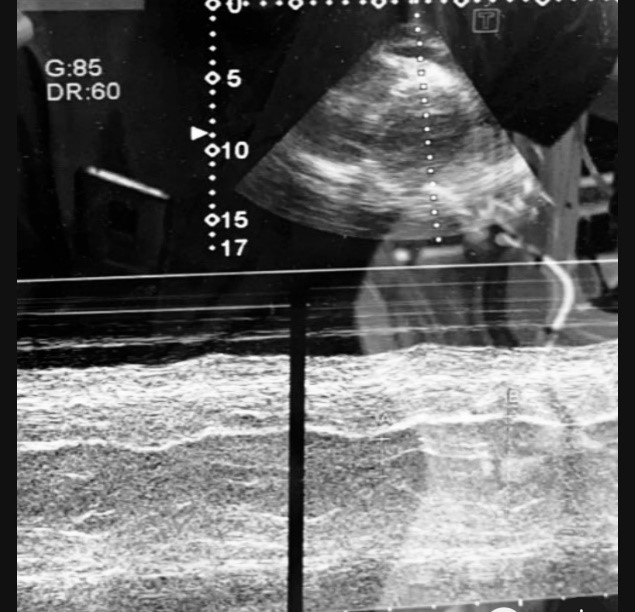

A 65-years-old male with a significant medical history of hypertension, a heavy smoking habit (2 packs per day) and a recent diagnosis of acute coronary infarction was scheduled for AAA repair. Preoperative imaging revealed an infrarenal abdominal aortic aneurysm measuring 11cm in length and 4.5cm in diameter, with circumferential mural thrombosis and peripheral hyperdensity, indicating a high risk of rupture. Fourteen days before surgery, the patient complained of chest pain and breathing difficulties, prompting an electrocardiogram revealing occurrence of an acute myocardial infarction demanding coronary angiography and subsequent stenting. The angiography revealed severe stenosis in the left anterior descending artery (95%) and left main (99%), which necessitated the placement of two stents. Unfortunately, a coronary artery rupture occurred during the stenting, and the patient has developed a subsequent hemopericardium. Echocardiography has demonstrated pericardial effusion and presence of fresh coagulum inside pericardial sac, warranting further evaluation. A second coronary angiography the next day showed no extravasation of contrast, but the pericardium was observed to be thickened and filled with blood without any influence of the cardiac filling and contractility. The patient was treated with Clopidogrel 75mg and Aspirin 100mg due to coronary artery stenting, but because of the present abdominal pain and CT findings showing a high risk of AAA rupture, he was scheduled for a AAA surgical repair. High-risk informed consent due to possible anesthetic and surgery related complications was obtained from the patient prior to intervention. Due to the risk of stent thrombosis dual antiaggregating therapy was sustained even at the day of surgery. The anesthetic management of this complex case was made under standard noninvasive and invasive measurement of arterial blood pressure after right radial arterial line placement, which was inserted after a successful Allen’s test, as well as central venous pressure measurement after right jugular central line insertion using ultrasound. Vital signs before surgery showed hemodynamic instability with hypotension (90/50mmHg), a heart rate of 120bpm and oxygen saturation of 93%. The patient was started on a noradrenaline infusion (8mg/50ml) at a rate of 0.1mcg/kg/min to address the hypotension. Induction in anesthesia was made with a careful titrating of anesthetic medications using Midazolam 1mg, Ketamine 100mg, Propofol 20mg, Fentanyl 50mcg and muscle relaxation was provided by Cisatracurium 10mg. After induction and successful placement of an endotracheal tube with No. 8.5, the patient was ventilated using a pressure-control volume-guaranteed mode. Intraoperatively, anesthesia was maintained with sevoflurane (1% with MAC 0.5-0.7) while analgesia was provided by continuous infusion of remifentanil (2mg/50ml) at 0.05mcg/kg/min, Metamizole Sodium 2.5g and Acetaminophen 1g. Because of sustained hemodynamic instability with hypotension and tachycardia with heart rate of 120-130 beats per minute and requirement of escalating doses of continuous Norepinephrine infusion, we have made an intraoperative transthoracic echocardiography. Due to surgical isolation just below the fourth rib transthoracic examination was difficult and incomplete, but it has provided significant data for the hemodynamics of the patient leading us to a substantial change in intraoperative treatment. Actually, the echocardiographic findings have shown persistence of a pericardial effusion mentioned before without influence of right ventricular filling nor systolic function which ruled out the diagnosis of pericardial tamponade as a cause of hemodynamic instability (Figure 1). Echocardiographic examination has shown presence of atrial fibrillation with inappropriate left ventricular contraction seen by eyeballing and confirmed in M-mode tracing of the left ventricle. Also, absence of the atrial kick on transmitral doppler was confirmed which is considered as a pathognomonic sign for AFF. Left atrial enlargement was met without any thrombotic masses in the left heart. After the echocardiographic examination, the patient has received Metoprolol 5mg in slow i.v. bolus which resulted in pharmacological cardioversion leading to converting the patient into sinus rhythm with HR of 65 and hemodynamic stabilization with SBP of >120mmHg and DBP >70 and MAP greater than 65mmHg, in order to maintain adequate perfusion. Another quick point of care – echocardiographic evaluation was made later on which has confirmed conversion of atrial fibrillation into sinus rhythm with clear distinction of systole and diastole on the left ventricular M-mode tracing, and significant improvement of the cardiac output due to establishment of left ventricular competence (Figure 2). After pharmacological rhythm conversion into sinus rhythm, improvement of hemodynamics was met, and we have lowered the intraoperative doses of norepinephrine to 0.02mcg/kg/min. During the surgery we have used cell salvage in order to minimize blood loss and maintain hemodynamic stability. The surgery has lasted for 5 hours, with an aortic clamping time of approximately one hour and 10 minutes. After successful performance of surgical technique and fulfillment of extubation criteria, the patient was safely extubated in the operating room and transferred to the Post Anesthesia Care Unit for further monitoring. Prior to transport I PACU, he was completely hemodynamically stable without need of any vasopressors nor inotropes. Postoperatively the patient has received metoprolol once daily with no adverse events until hospital discharge.

Figure 1. Pericardial effusion without impairment of ventricular filling.